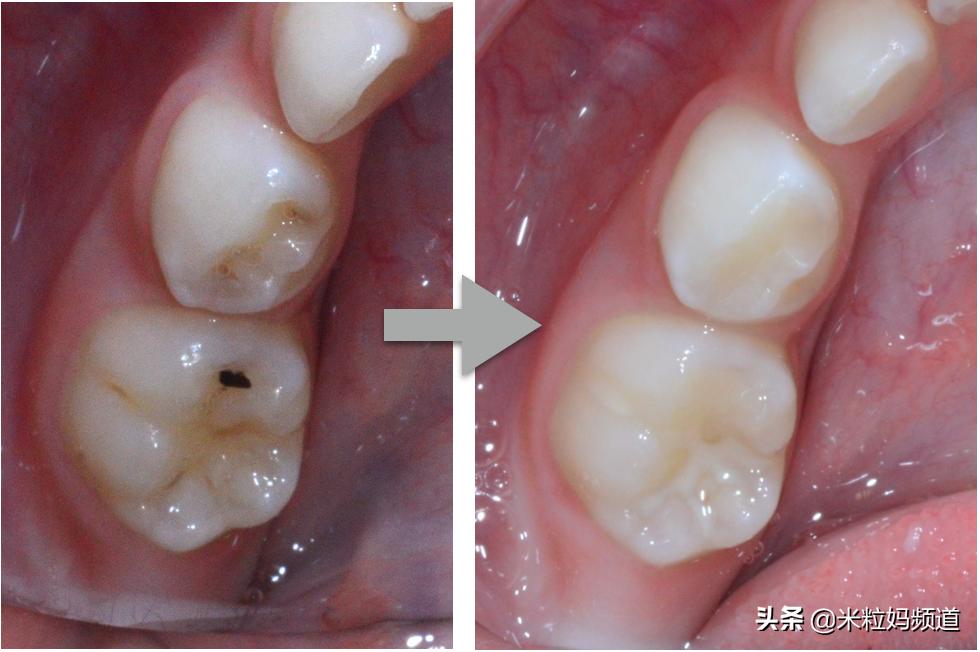

臼齿咬合面

臼齿咬合面有许多沟纹,特别是那些又甜又黏的食物最容易堆积陷在凹槽里,更糟糕的是,这个部位牙刷又刷不到,完全是清洁的死角,就妥妥的变成牙菌斑滋生,蛀牙发生的绝佳位置了。

很多孩子臼齿咬合面的沟隙看起来是黑黑的,很多家长会以为这就算是蛀牙,也只是一点点,反正乳牙掉了以后换恒齿就没事了,其实这样的观念大错特错!

不要小看这一点点的蛀牙,它很可能就像冰山一角一样,上面看起来只有一点点,其实底下已经快蛀到牙髓腔(下图粉红色的地方),而发生这种状况时,通常牙齿就开始痛了,也就是要做根管治疗(抽神经)的时候了。